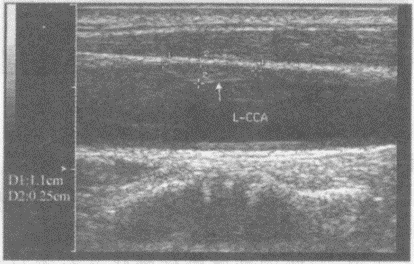

临床资料:男,56岁,常规体检,确诊高血压、糖尿病5年。超声综合描述:双侧颈总动脉中内膜厚度0.13cm,左侧颈总动脉中段管腔内可见1.1cm×0.25cm中等回声,后方无声影。

超声提示()。

A.双侧颈动脉粥样硬化

B.双侧颈动脉粥样硬化并左颈总动脉中段软斑形成

C.双侧颈动脉粥样硬化并钙化斑形成

D.颈动脉正常声像图